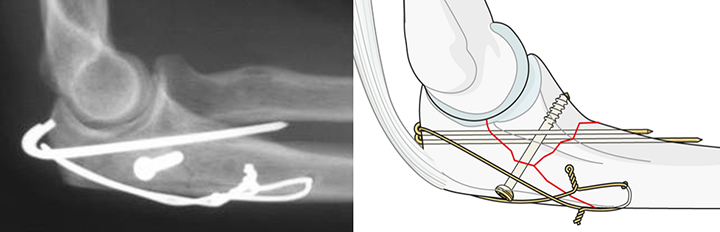

一般に、小さなかけらによる骨折が多いので、細い針金を巻き、鋼線や骨ネジなどを用いて固定する方法が良く行われています(図2)。また骨折した骨のかけらが、細かく裂けている場合や、怪我した方が高齢の場合、あるいは脆い骨による骨折の場合は、金属のプレートを用いる方法も行われています(図3)。

図2 細い針金を巻き、鋼線や骨ネジを用いて骨のかけらを固定する。

(テンションバンド固定法 https://www.aofoundation.org)